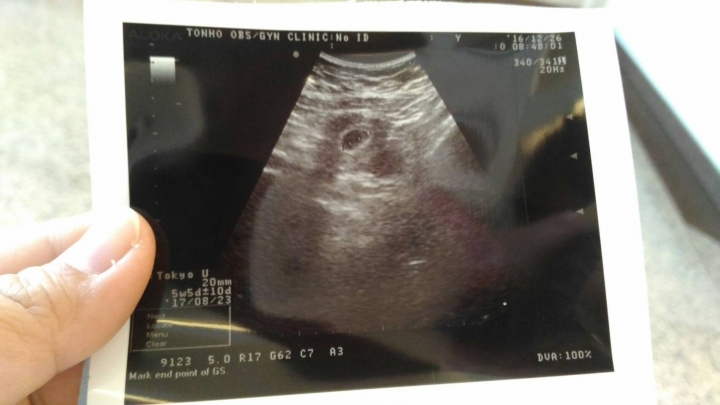

我覺得很怪 今天又換了一間婦產科照~變成2公分~還照的出來五週又五天~